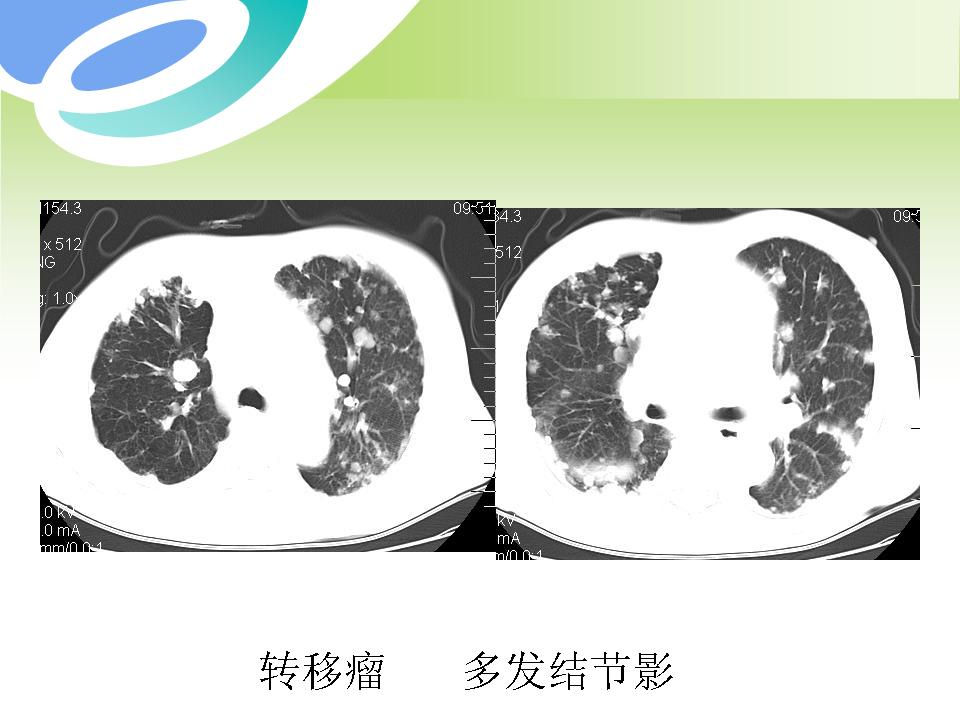

肺部病变的CT基本征象